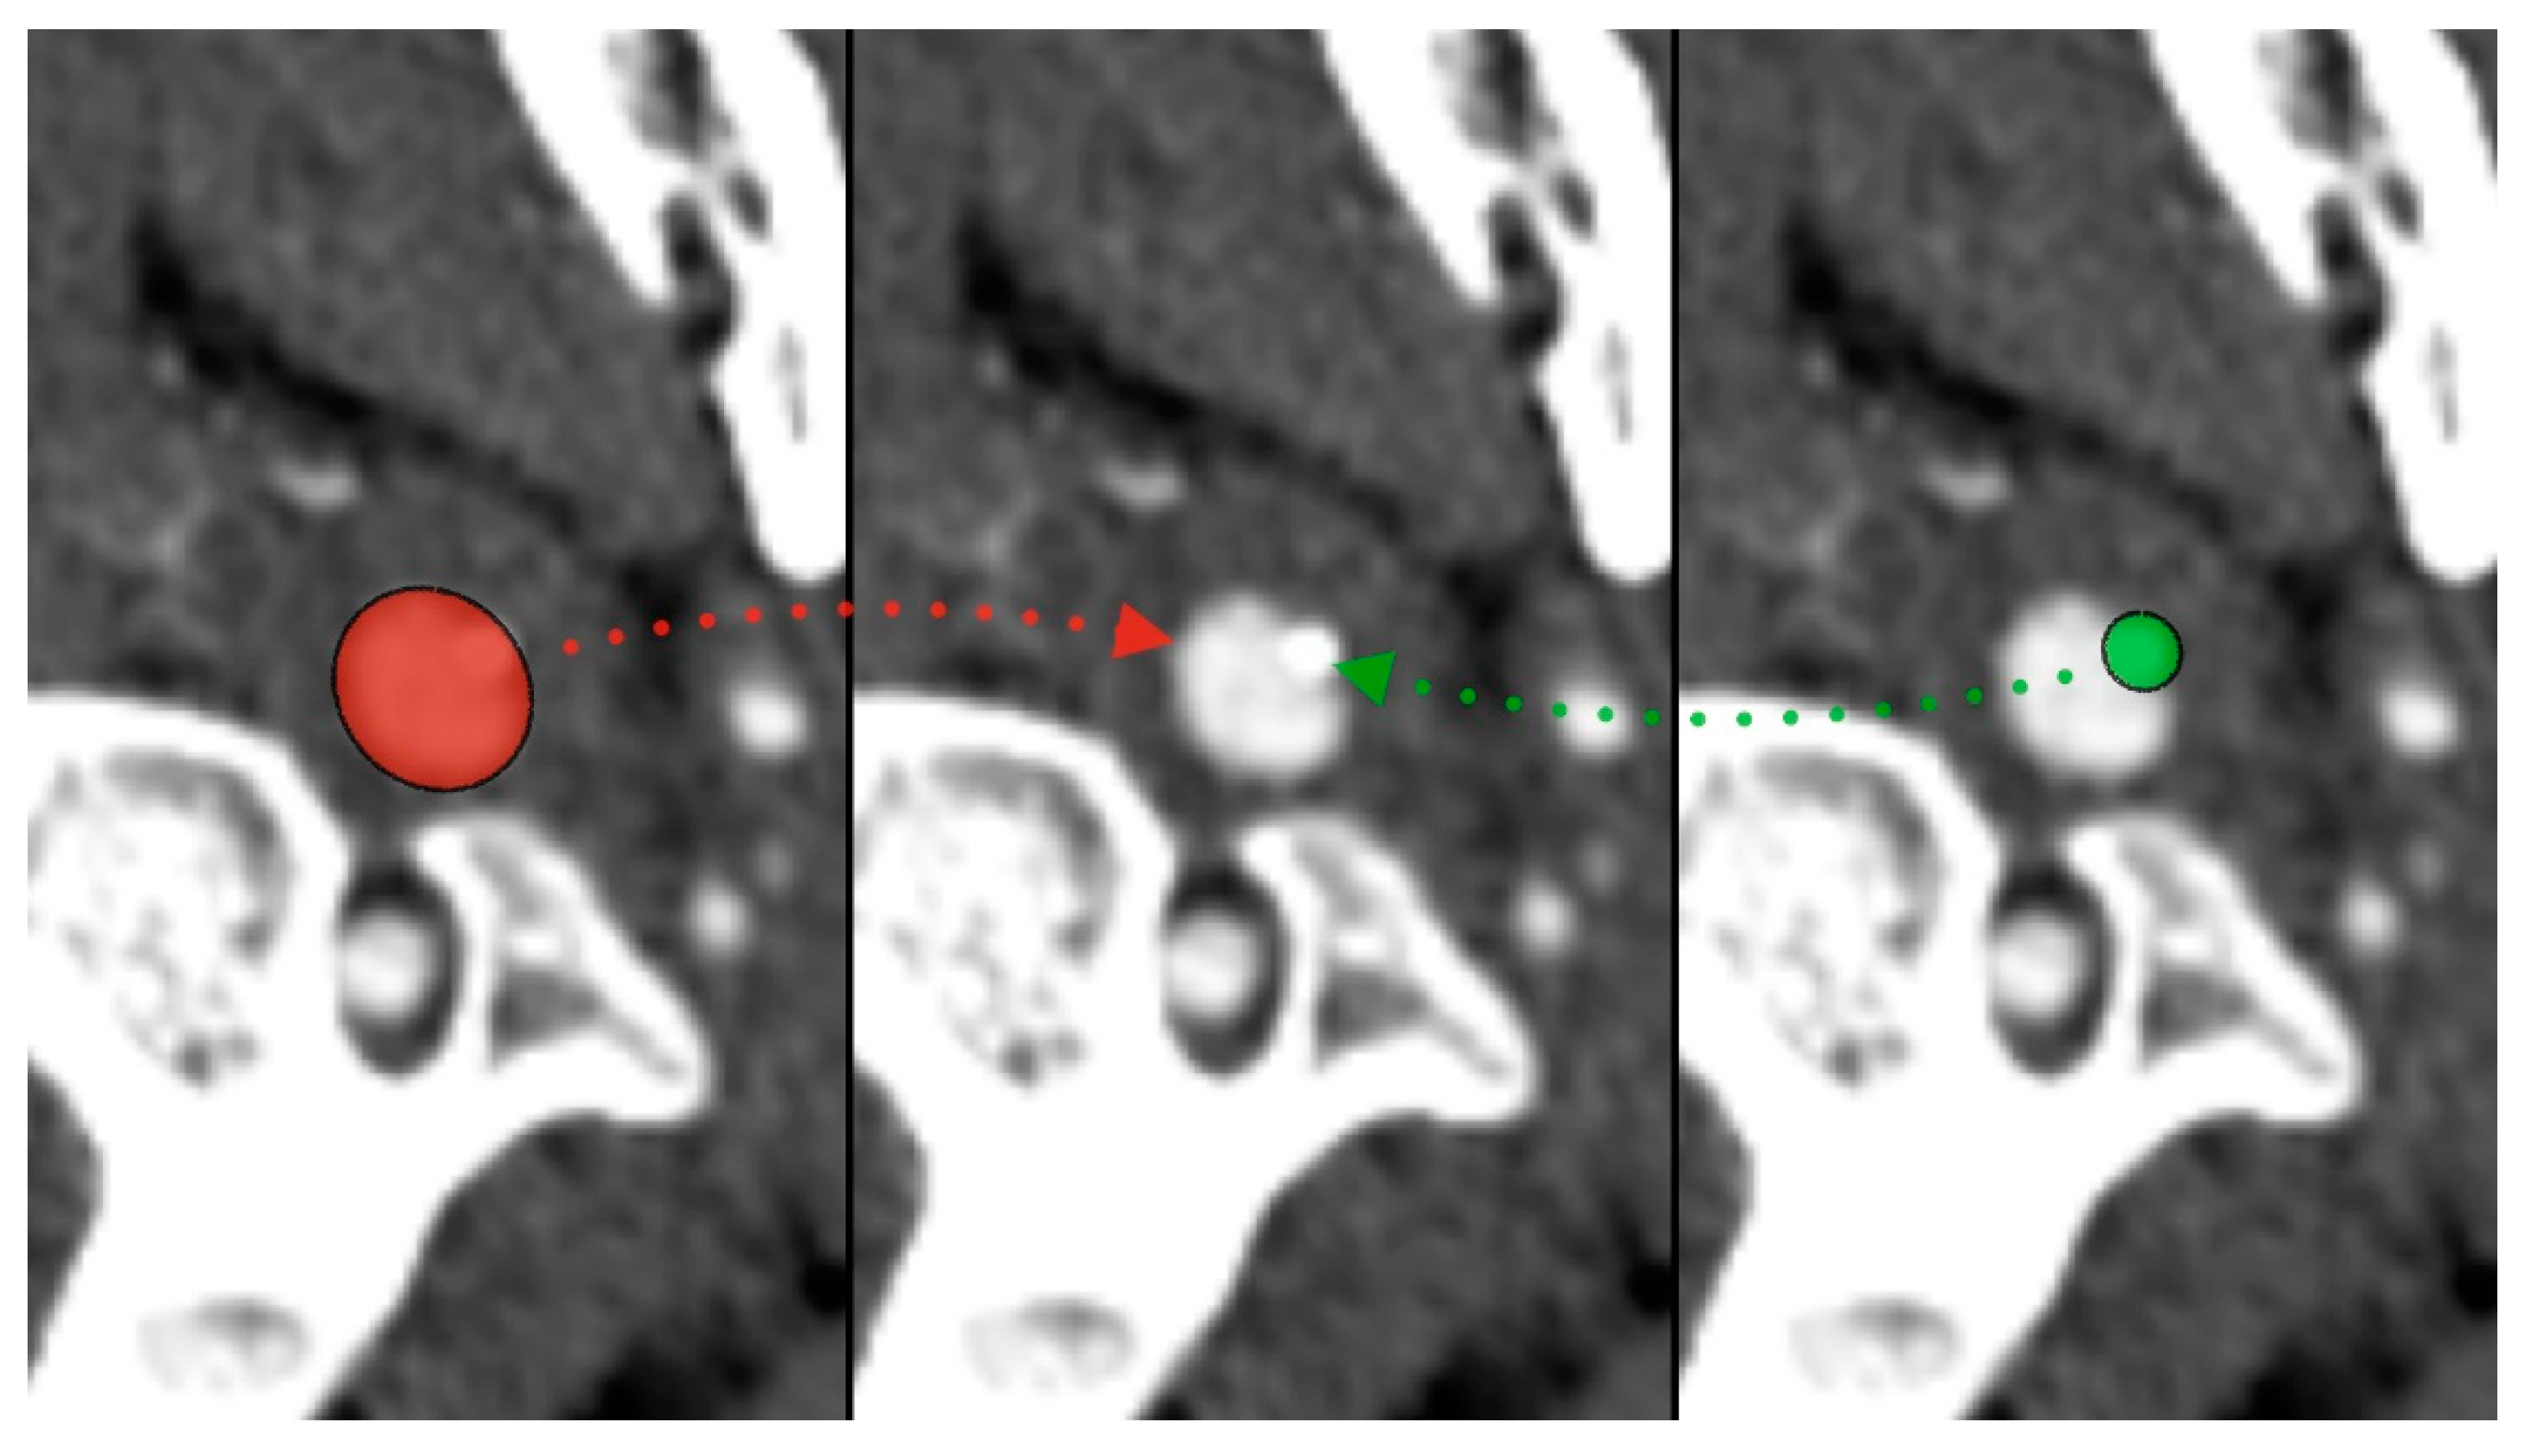

During the CT angiography (CTA) evaluation of thrombolytic treatment, the radiologist identified a bony structure that reduced the diameter of the left internal carotid artery (LICA) from 14 to 7 mm. Three-dimensional reconstruction identified the styloid process, measuring 29 mm, compressing the vessel (Figure 1 and Figure 2). Vascular surgeons suggested LICA decompression without stenting. Consequently, the patient was qualified for styloidectomy and was transferred to the Cranio-Maxillo-Facial Department.

Figure 1. Styloid process compressing left internal carotid artery—red (ICA), green (styloid).